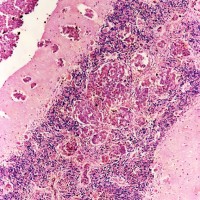

悪性黒色腫(melanoma) の細胞で,多核の細胞や,細胞の大小不同,核の異型性が目立ち悪性腫瘍の所見です。右の画像では大小の血管が腫瘍組織の間に発達しています。非常に血管に富む腫瘍です。